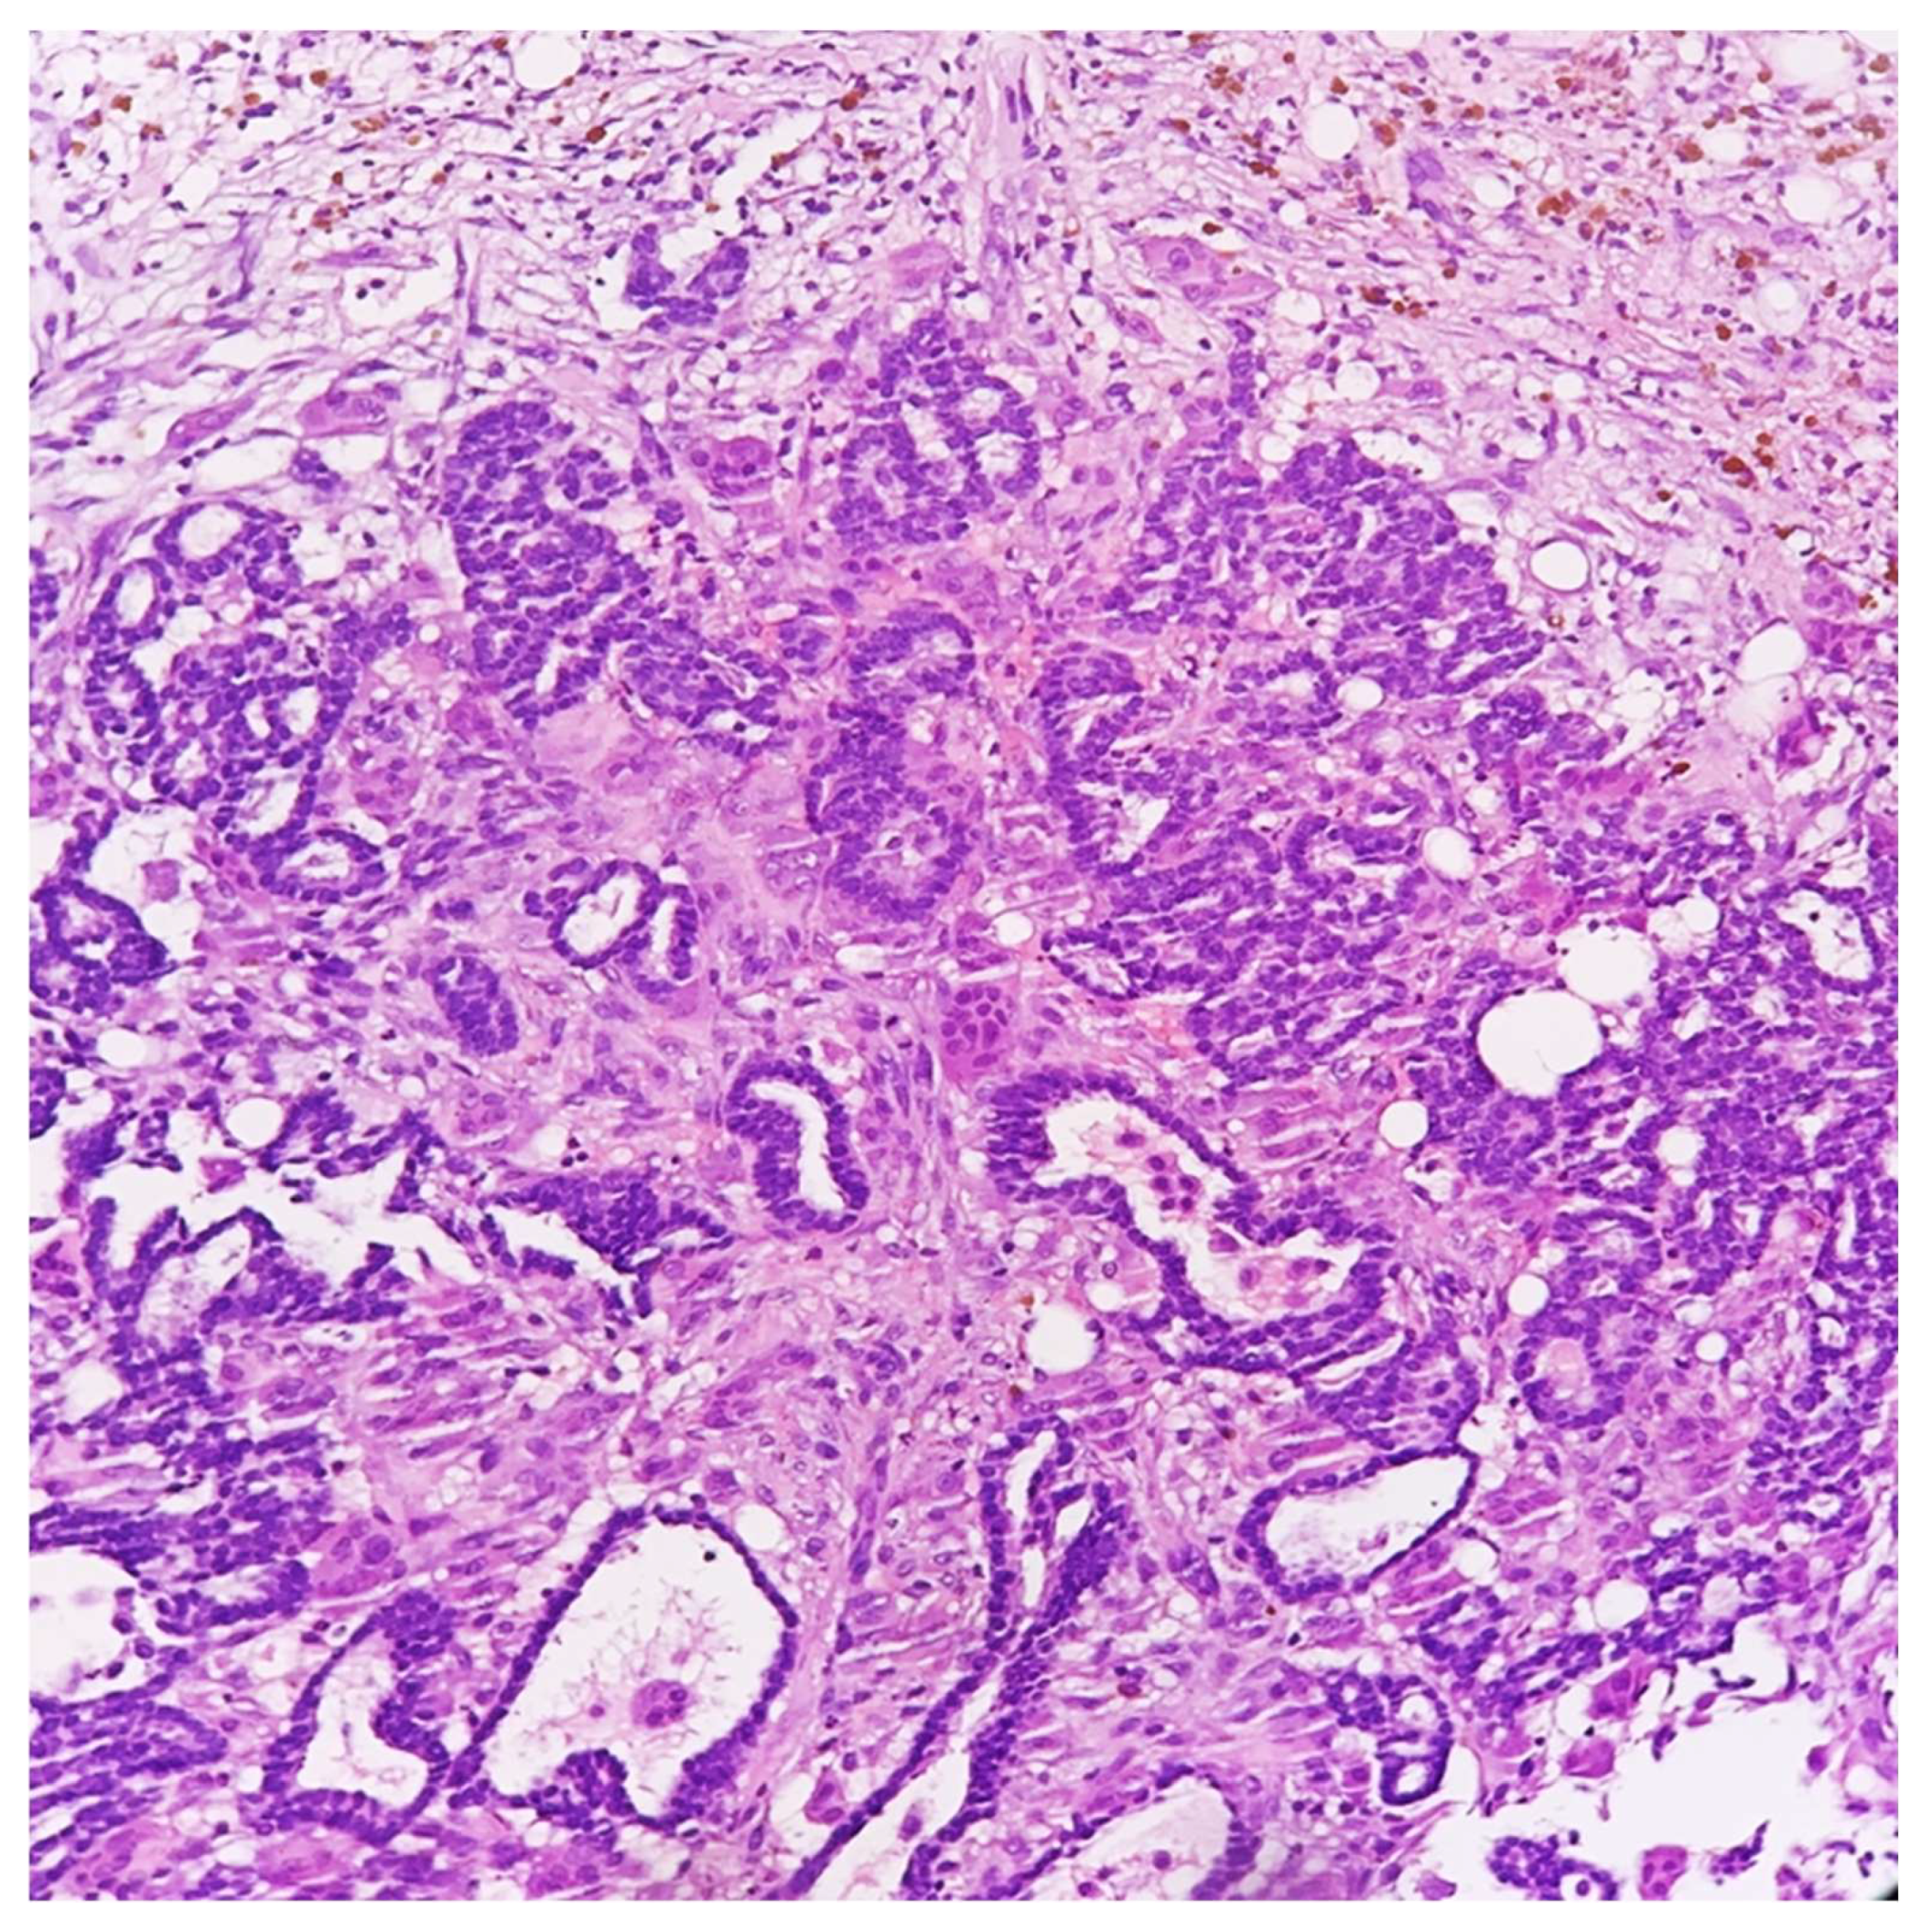

Microscopically, the lesion showed a fibrous reaction at the site of the previous core biopsy, along with adjacent foci of ductal carcinoma in situ and a small (3-millimeter) residual part of invasive carcinoma, grade 2. Surprisingly, even after a meticulous examination, osteoclast-like giant cells were no longer detected in the surgical specimen (Figure 3 and Figure 4).

Figure 3. Histological section from quadrantectomy specimen showing fibrous reaction in the site of previous biopsy, along with foci of ductal carcinoma in situ and residual invasive carcinoma (HE, 25×).